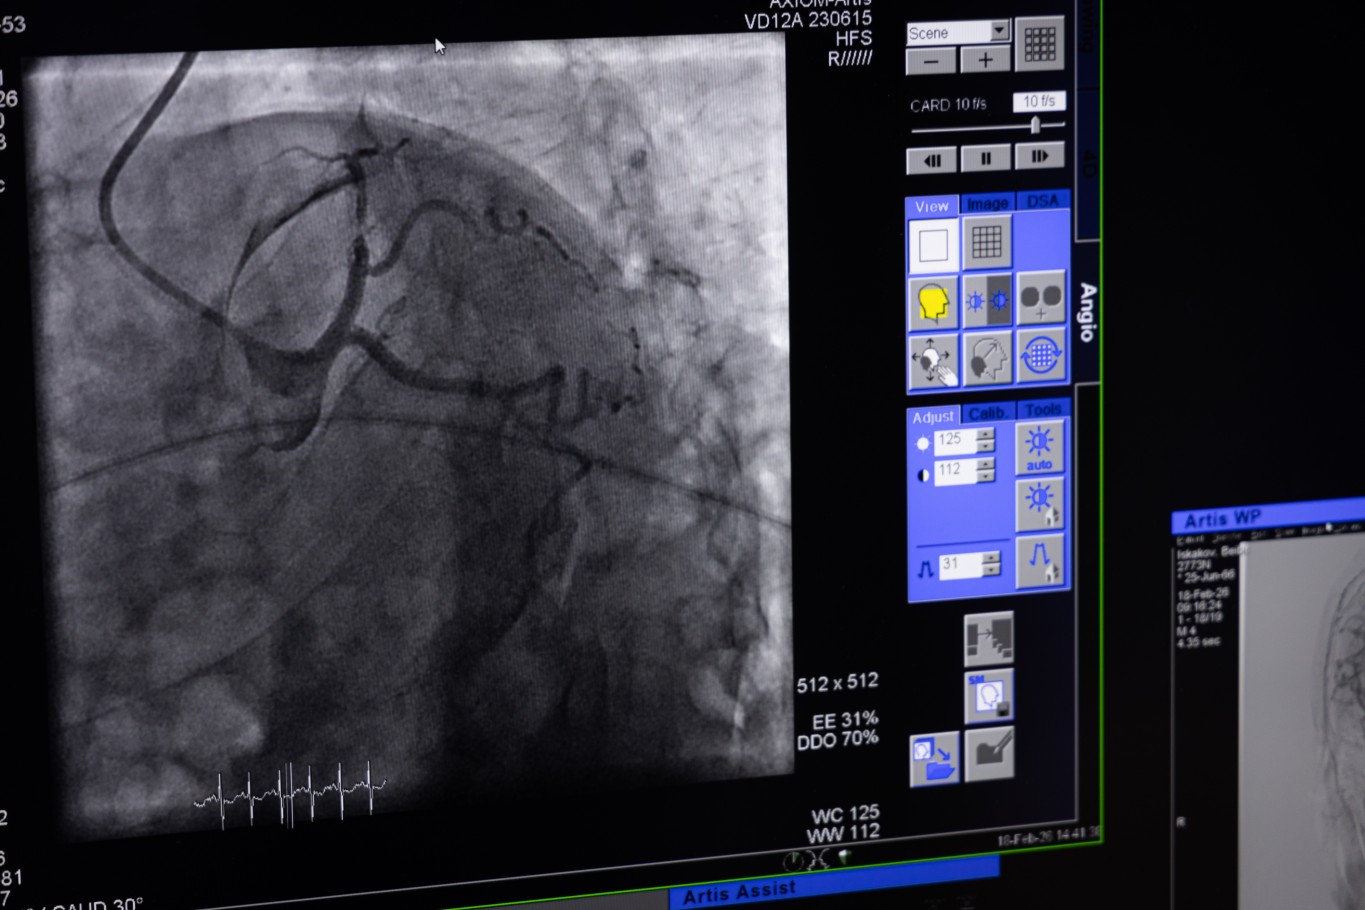

Стоит отметить, что в облбольнице уже есть ангиограф, но он нацелен на кардиологическую помощь, а новоприобретенный — более универсальный. С его помощью можно проводить малоинвазивные операции и использовать его в диагностических целях.

Новый ангиограф позволяет оказывать помощь пациентам с сосудистыми, кардиологическими, нейрохирургическими и аритмологическими проблемами.

— В принципе, везде, где есть сосуды, на этом ангиографе можно будет увидеть и выполнить какую-либо манипуляцию. Также возможны различные эмболизации доброкачественных опухолей матки, простаты, щитовидной железы, печени. Все это мы можем делать на этом ангиографе, — отмечает Сергей Сальверович.

— Операции уже начали проводить. Разгрузили первый ангиограф, теперь работа ведется на двух аппаратах. Новый ангиограф в режиме реального времени поддерживает 3D-визуализацию, он оснащен алгоритмами снижения лучевой нагрузки на пациента и медперсонал. В среднем обслуживается 17–18 пациентов в день. Самая распространенная операция — на сердце, — говорит замдиректора.